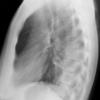

Case 2  Lingular pneum Lat

Date: 04/17/2005

Views: 6950